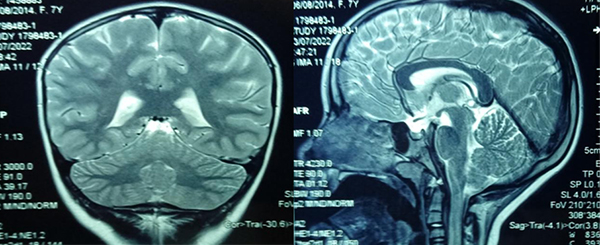

Figura 1: Caso ejemplo: paciente de 7 años. Derivada por cefaleas y disminución de la agudeza visual (corregida con anteojos). Seguimiento de dos años sin variantes en la IRM.

Nótese la característica circular de la lesión y contenido que resuena similar al L.C.R

Las características propias de un quiste simple de la región pineal son bien conocidas: imagen redondeada con contenido similar o ligeramente hipertenso en IRM en T1. En general sin refuerzo post contraste o alguna calcificación periférica. En la secuencia Flair la señal es alta, a menudo no suprime por completo, y en DWI-ADC no muestra restricción en la difusión.1,2,3,4